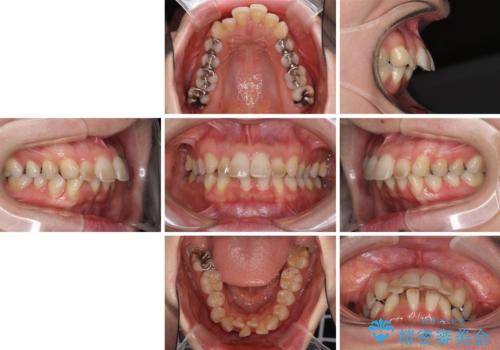

- 上下の出っ歯を気にして来院された患者様です。

口元を積極的に引っ込めるために、上下左右の第一小臼歯を4本抜歯することとしました。

元々ディープバイトのため、スペースを閉じている期間に上下前歯が接触してしまい、治療期間が想定よりも伸びてしまいました。